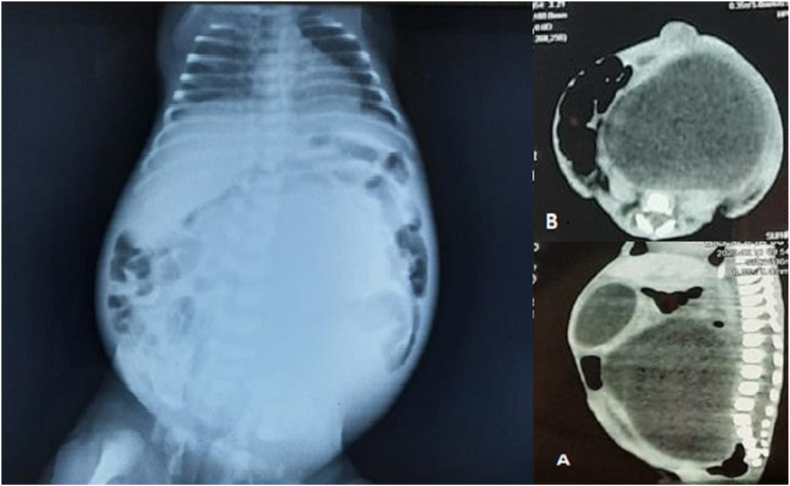

Fig. 2.

X-ray abdomen and computed tomography showing hydrometrocolpos compressing against the diaphragm causing respiratory distress.

Postnatal examination revealed a birth weight of 2.9 kg, a head circumference of 36 cm, and a length of 43 cm. Facial features were suggestive of trisomy 21. She was in respiratory distress that needed nasal oxygen at 2 L/min. On abdominal examination, there was a large cystic mass with no displacement. Upper and lower extremities had postaxial polydactyly with bilateral pes cavus (Fig. 1). Computed tomography and X-ray abdomen confirmed a pelvic cystic mass between the bladder and rectum, corresponding to a HMC (Fig. 2). Cystoscopy and genitography confirmed HMC and a transverse vaginal septum. Echocardiography showed a patent foramen ovale with non-significant left to right shunt upon crying. On genetic testing there was mutation in MKS gene (604896). No mutation at Bardet-Beidel locus of MKS gene was observed (BBS6; 605231).